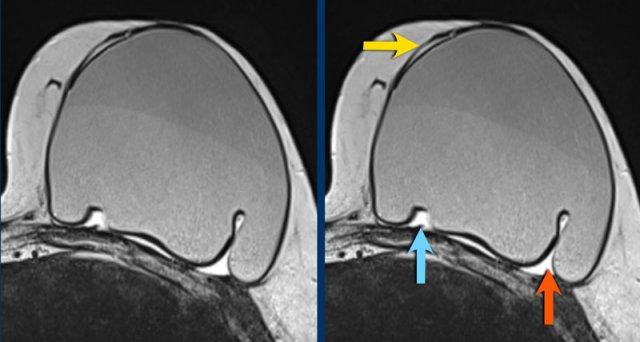

Đây là một ví dụ khác về các biểu hiện khác nhau của vỡ túi trong bao xơ, với silicone nằm ngoài vỏ túi nhưng còn trong bao xơ.

- Đường dưới bao xơ (subcapsular line) (mũi tên vàng)

- Dấu hiệu mũi (nose sign) (mũi tên xanh dương)

- Dấu hiệu giọt nước mắt (teardrop sign) (mũi tên đỏ)